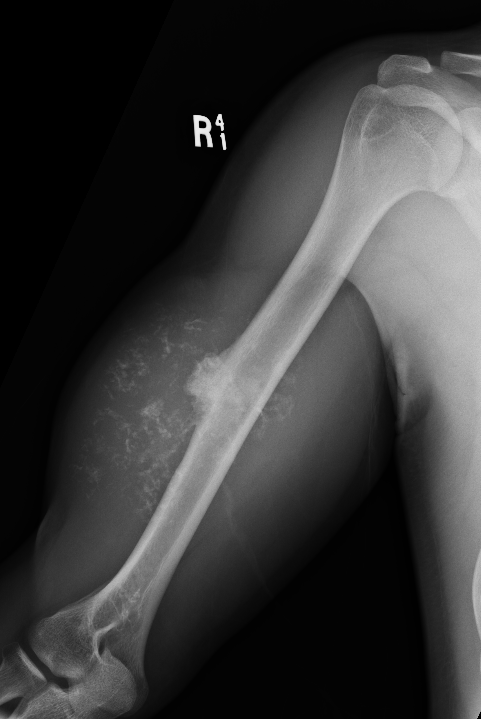

Enchondroma enlarging over time

Large calcification with endosteal scalloping humerus

Large calcified lesion with endosteal scalloping